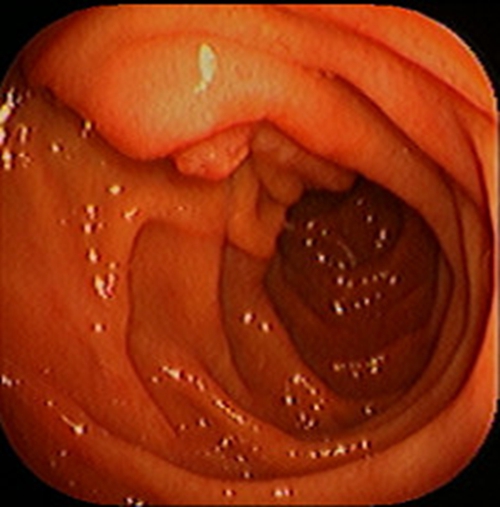

急性胃炎圖片

急性胃炎陽性表現

急性胃炎陽性的表現的

急性胃炎陽性的表現

急性胃炎陽性表現的

急性胃炎的陽性的表現的

急性胃炎的陽性的表現